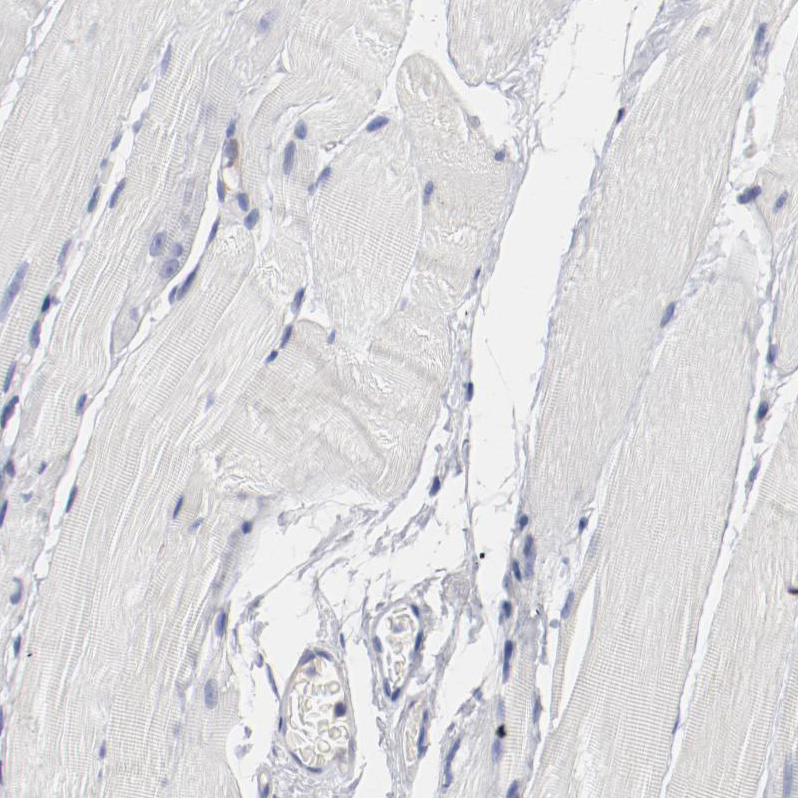

Immunohistochemical staining of human fallopian tube shows strong membranous positivity in glandular cells.